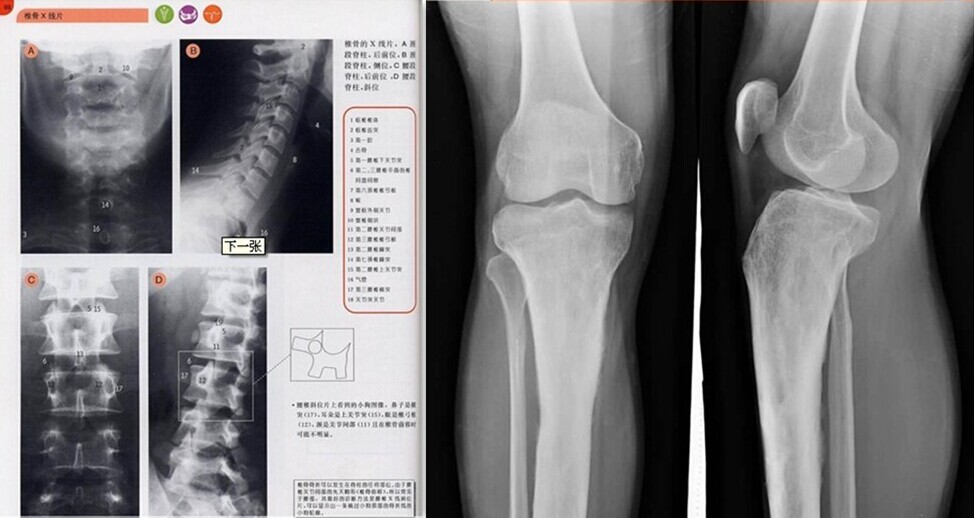

·Widely used for laser printing,the output of medical image,engineering drawing,